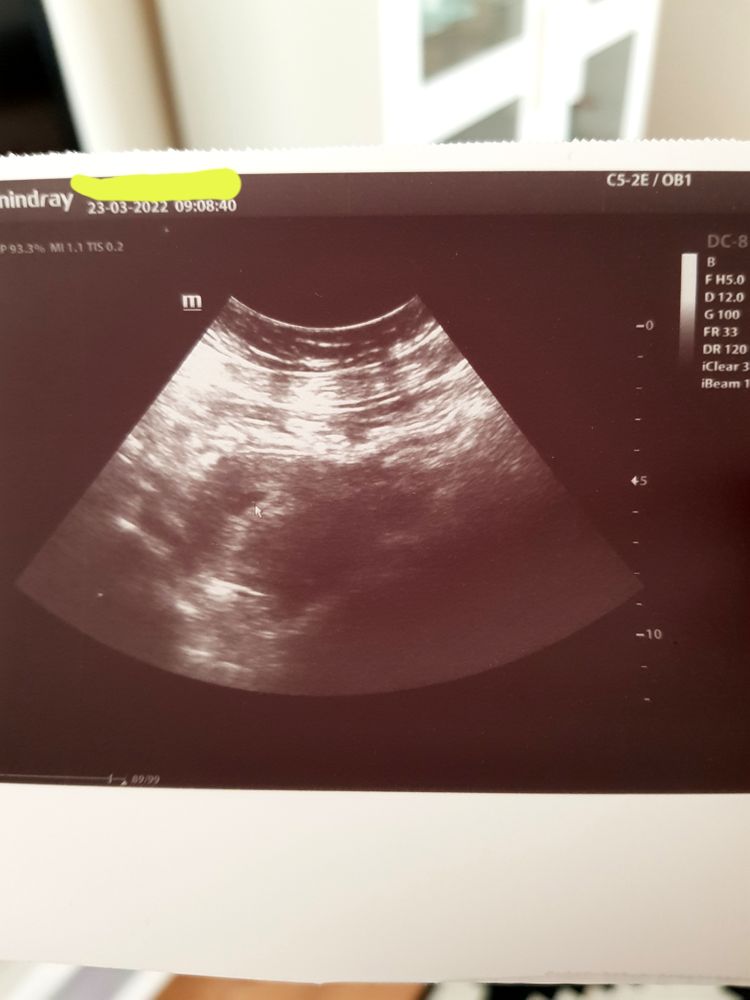

Первый снимок УЗИ.

В среду 23.03 была у Г.Вручила нам наш первый снимок😇